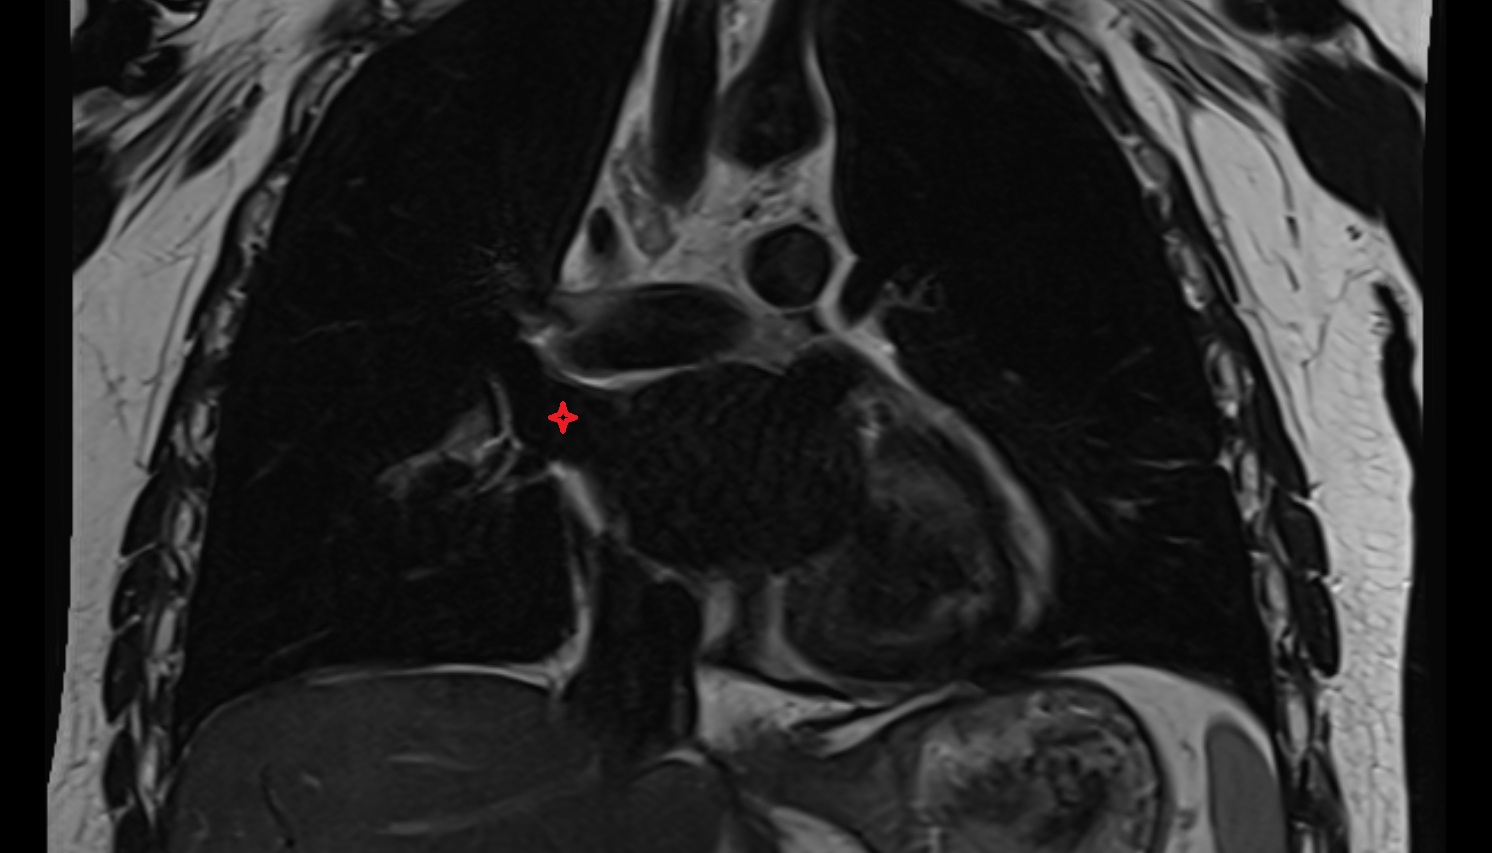

- Left anterior descending artery (LAD)

- Circumflex artery (LCx)

- Left main coronary artery (LMCA)

- Right coronary artery (RCA)